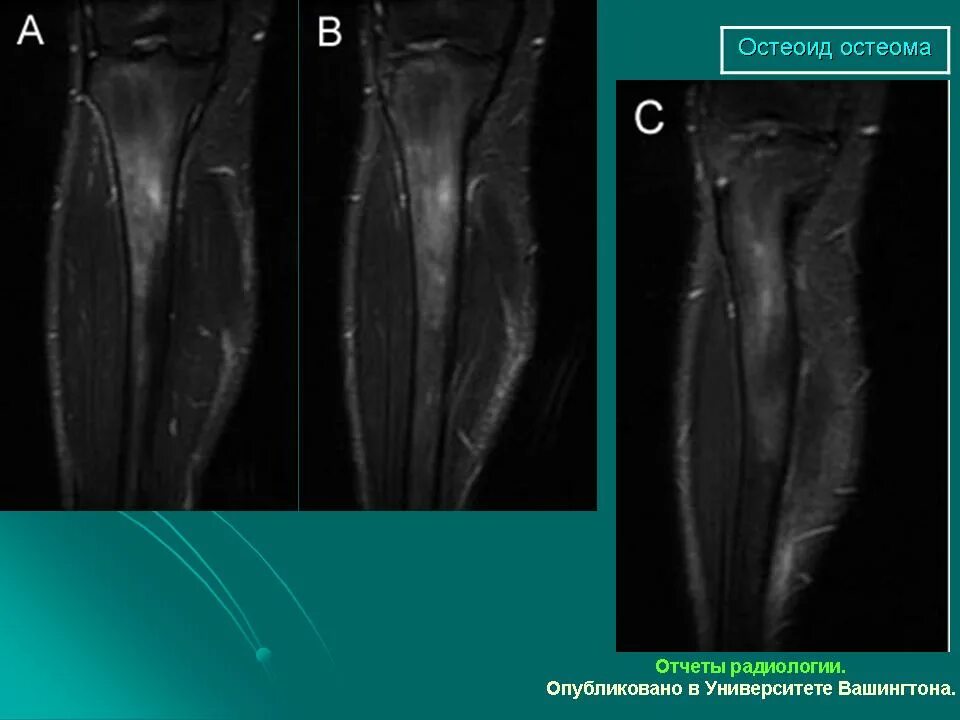

Остеома мрт